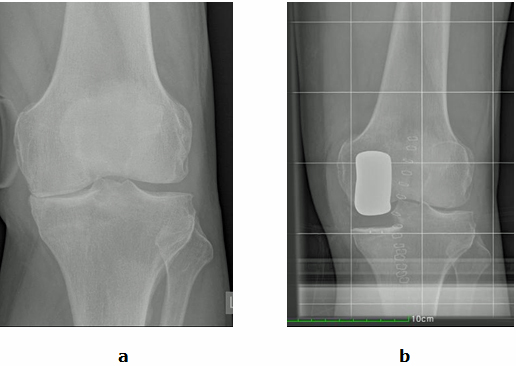

Abb.1: a Der Innere Gelenkspalt (Pfeil) ist aufgehoben. Der Äußere Gelenkspalt ist intakt. b Der Innere Gelenkspalt wurde durch eine Schlittenprotheseersetzt (Gelenkteilersatz).